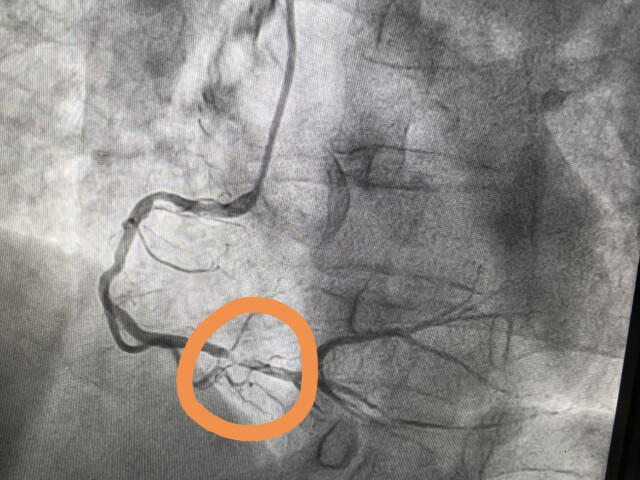

12点17分,120救护车绕过急诊和心血管内科病房,直接将童阿姨送入介入治疗室。早已准备就绪的心血管内科二病室副主任石为和副主任医师陈航第一时间为童阿姨进行冠脉造影检查,发现她有多根血管病变,其中右冠更是堵塞了99%!

明确了此次心梗的“罪犯”血管与治疗方案后,经验丰富的介入手术团队有条不紊地施行支架置入术。

12点52分,导丝通过病变血管,堵塞的血管恢复畅通,危机解除,童阿姨转危为安。